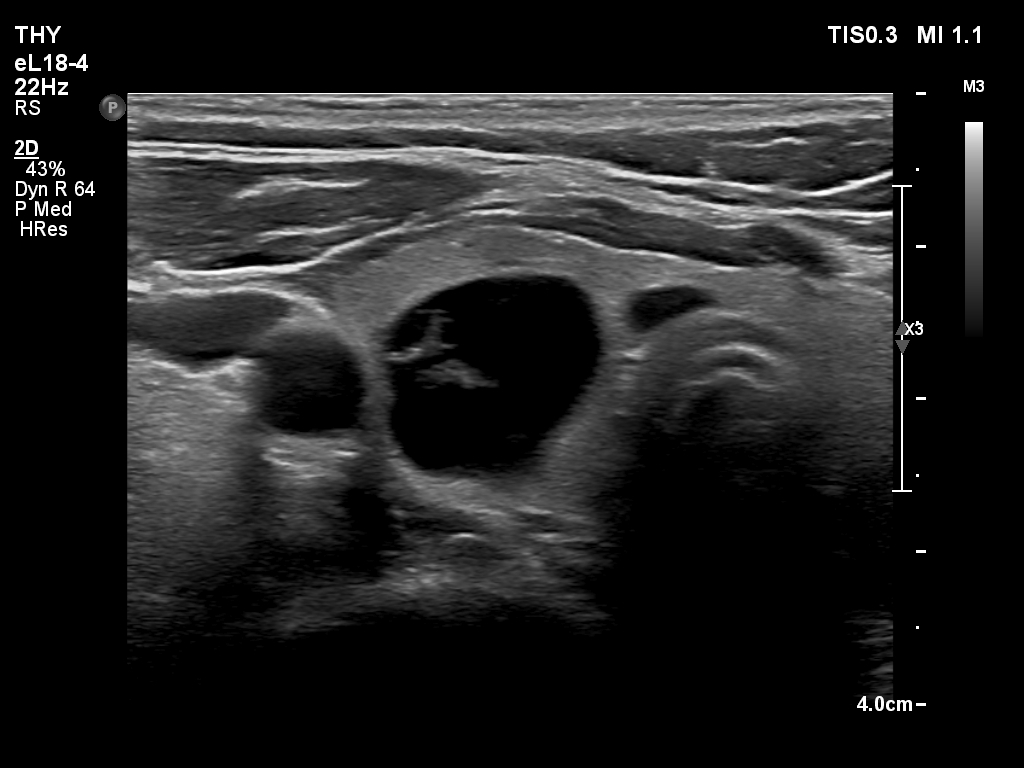

Ultrasonography. The thyroid was echonormal and had multiple nodules. There were cystic areas, an almost completely cystic nodule, and a dominantly solid nodule in the right lobe. The left lobe had three lesions. The upper solid lesion was the one we treated 16 years ago. The middle lesion was a dominantly solid while the lower one seemed to be a pure cyst. The dimensions of the nodule which has been treated with sclerotherapy were 10x11x13 mm (width, depth and length, respectively). There was a large cystic nodule in the upper pole of the left lobe. The lesion showed relatively large hyperechogenic granules. There were multiple enlarged lymph nodes lateral to the left lobe, two of largest were cystic.